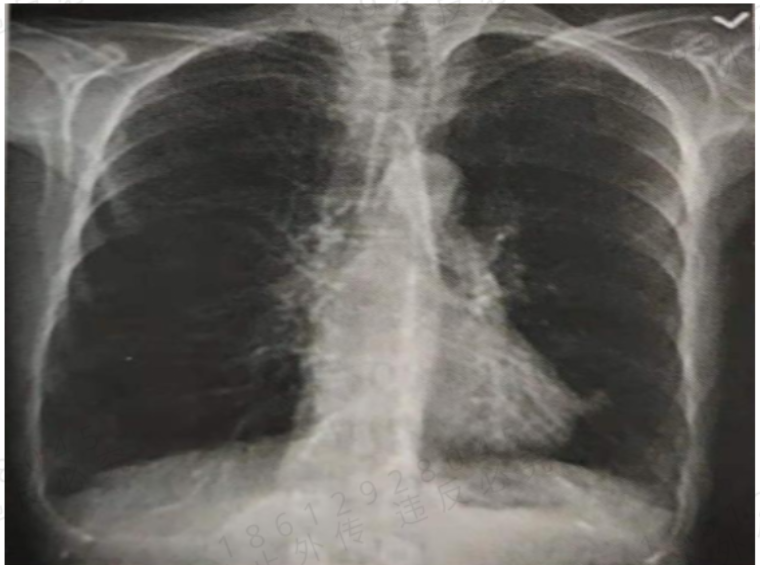

6、患者男,70岁。进行性活动后呼吸困难7年。既往:吸烟30年,30支/d。查体:桶状胸,双肺呼吸音低下,肺动脉听诊区第二心音亢进,剑突下搏动增强,双下肢可凹陷性水肿。X线如图。肺功能:FEV./FVC0.45,FEV,占预计值的45%,RVTLC67%,TLC占预计值的150%,一口气呼吸法DLCO-sb占预计值的60%,支气管舒张实验:FEV,改善 4.5%(30ml)。